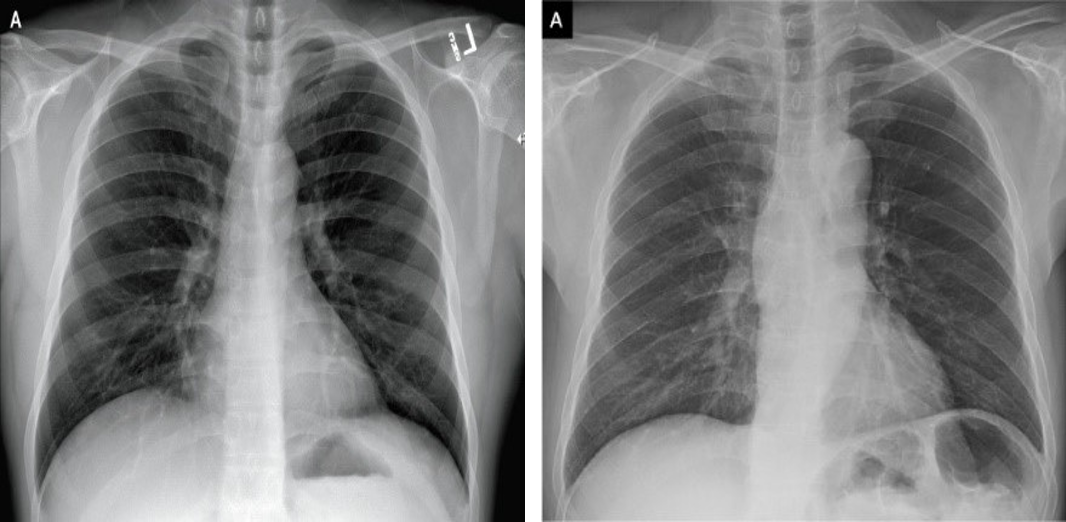

From a pictorial perspective of radiological images, CXR is the less sensitive modality with ground glass densities (GGO) easily detectable on CT but not CXR; CXR densities often appear hazy while CT densities have a clear contrast. However, reticular opacities are often more apparent on CXR than on CT. On baseline CXR, consolidations are the most common finding, with COVID-19 and viral pneumonia producing lung opacities in multiple lobes as opposed to one in bacterial pneumonia which tends to be unilateral. COVID-19 pneumonia has prominent peripheral air space opacities which are readily identified by both CT and CXR with CT reporting peripheral lung distribution in 33-86% of cases [4, 5]. Diffuse air space diseases such as acute respiratory distress syndrome (ARDS) demonstrate similar patterns to CXR, but these COVID-19 lung opacities rapidly evolve into a diffuse coalescent or consolidative pattern with 1-3 weeks of symptom onset [6, 7]. One study reported that of 64 patients, consolidation was found in (30/64, 47%) of patients while GGO was found in (21/64, 33%). Common distribution locations included peripheral (26/64, 41%) and lower zone (32/64, 50%), with most showing bilateral involvement (32/64, 50%) [1]. Although very uncommon, pleural effusions were found in a small number of cases.

In this study, 261 COVID-19 chest X-ray images have been obtained from the open-source COVID-19-CT-CXR dataset [9]. These images were extracted from figures, associated captions, and subfigures in COVID-19 articles from the PubMed Central Open Access (PMC-OA) subset. Most figures found in the PMC-OA articles are compound figures, each consisting of several subfigures often being of multiple categories such as CT, CXR, or an assortment of 26 other scientific figures. A deep-learning model was designed to distinguish compound figures from other figure types [9]. The designed deep-learning model is a convolutional neural network pretrained on the ImageCLEF Medical dataset [10].